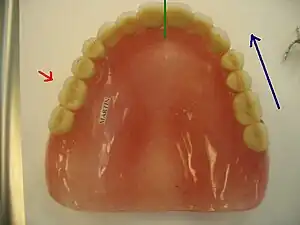

- Palatal

- The side of a tooth adjacent to (or the direction toward) the palate, as opposed to buccal, labial or vestibular which refer to the side of a tooth adjacent to (or the direction toward) the inside of the cheek, lips and vestibule of the mouth respectively. This term is strictly used in the maxilla.[1]